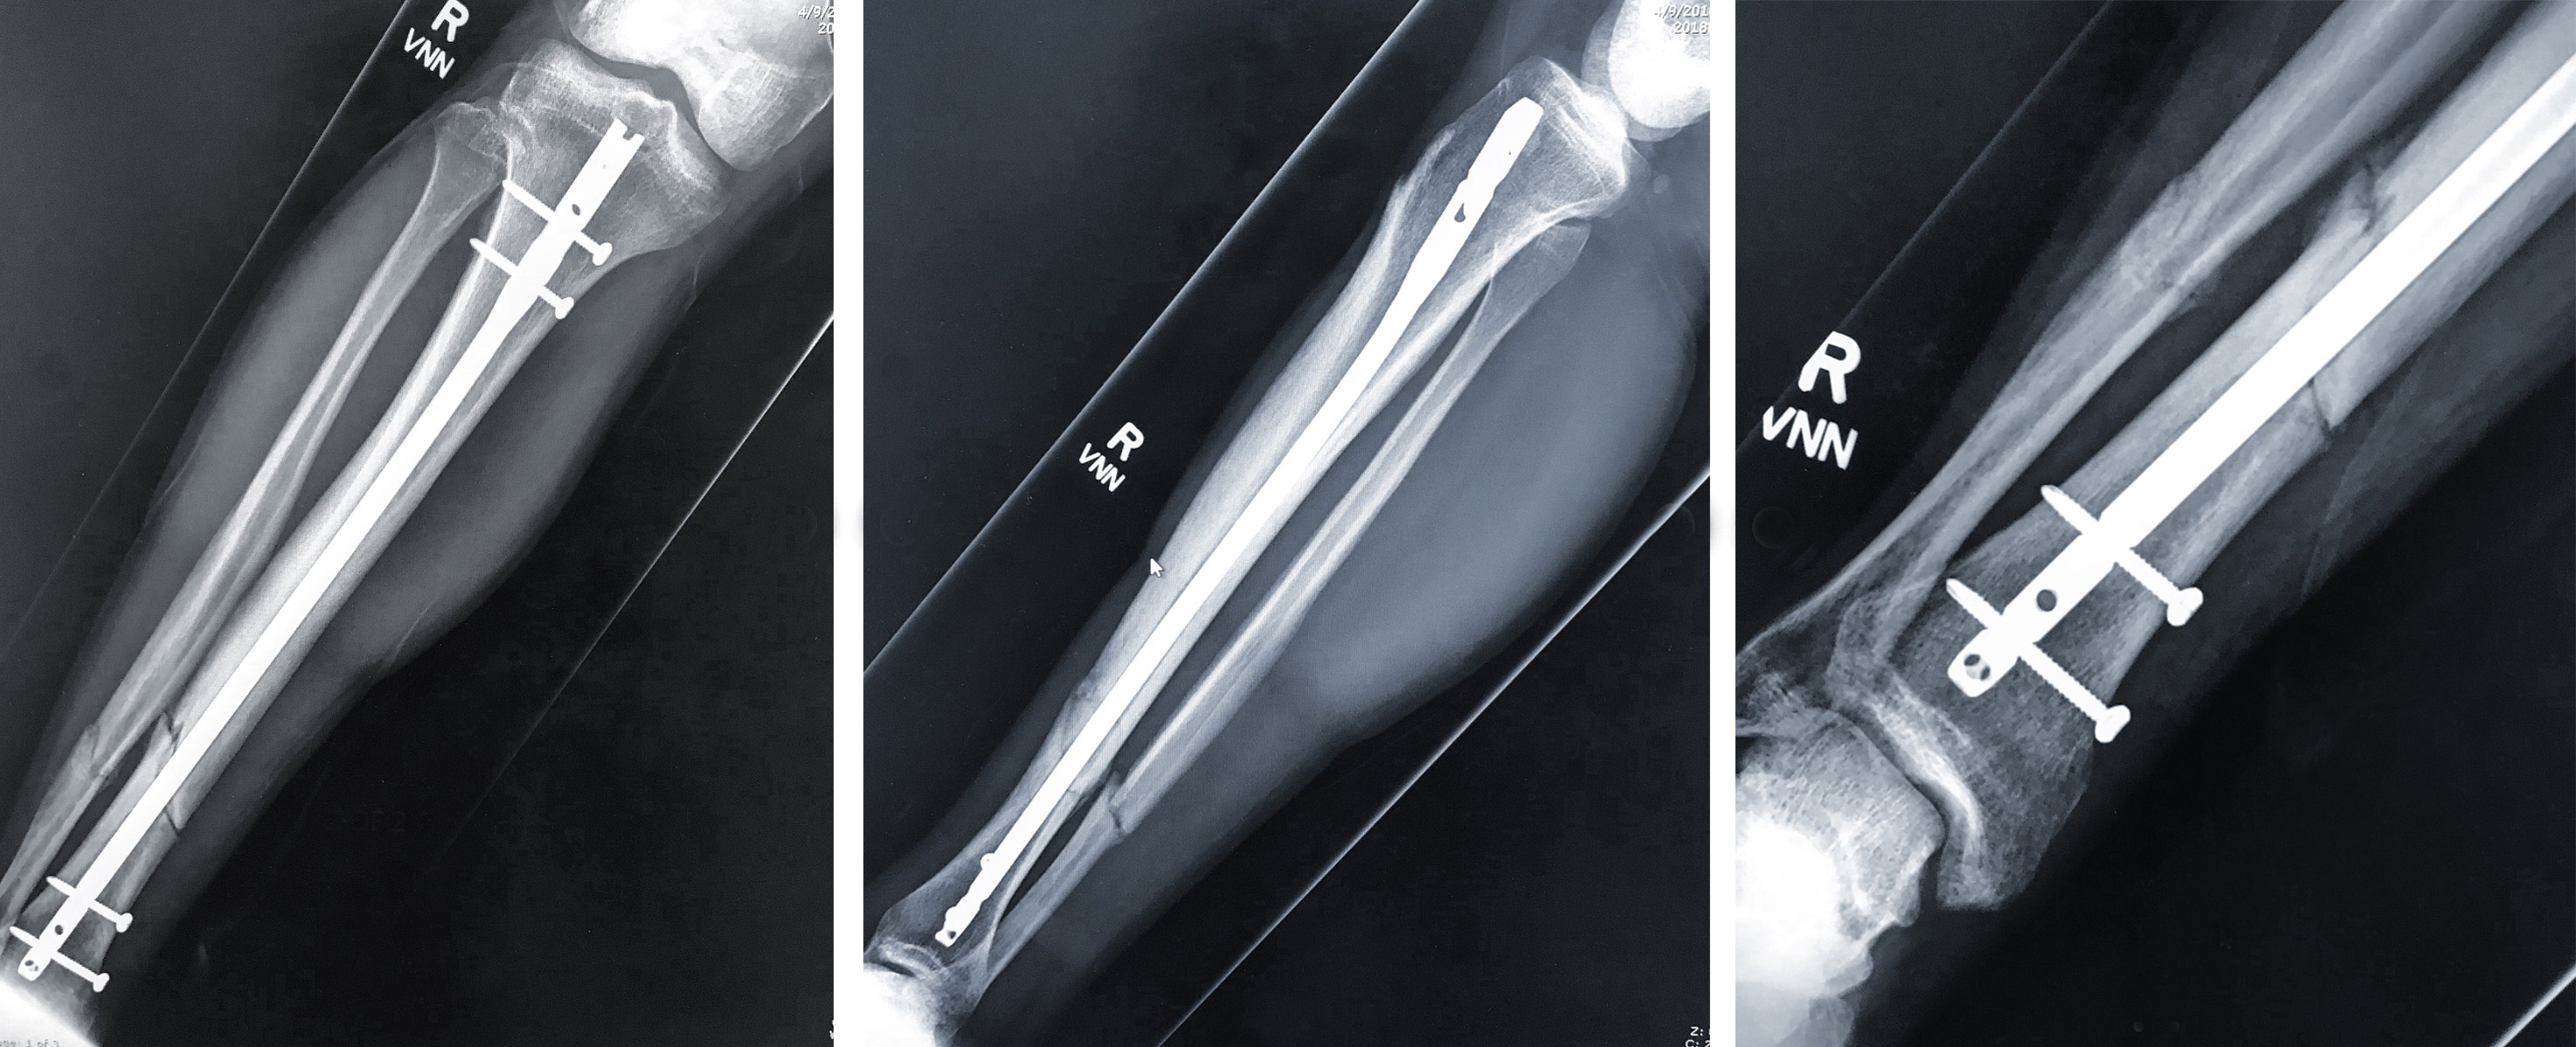

jesse leg.jpg

X-Rays showing the full extent of the snap, so gnarly!